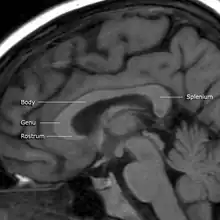

MRI of corpus callosum and its named parts

The corpus callosum has four main parts – individual nerve tracts that connect different parts of the hemispheres. These are the rostrum, the genu, the trunk or body, and the splenium.[4] A narrowed part between the trunk and the splenium is known as the isthmus. Fibres from the trunk and the splenium known together as the tapetum form the roof of each lateral ventricle.[6]

The front part of the corpus callosum, towards the frontal lobes, is called the genu ("knee"). The genu curves downward and backward in front of the septum pellucidum, diminishing greatly in thickness. The lower, much thinner part is the rostrum and is connected below with the lamina terminalis, which stretches from the interventricular foramina to the recess at the base of the optic stalk. The rostrum is named for its resemblance to a bird's beak.

The end part of the corpus callosum, towards the cerebellum, is called the splenium. This is the thickest part, and overlaps the tela choroidea of the third ventricle and the midbrain, and ends in a thick, convex, free border. Splenium translates as "bandage" in Greek.

The trunk of the corpus callosum lies between the splenium and the genu.